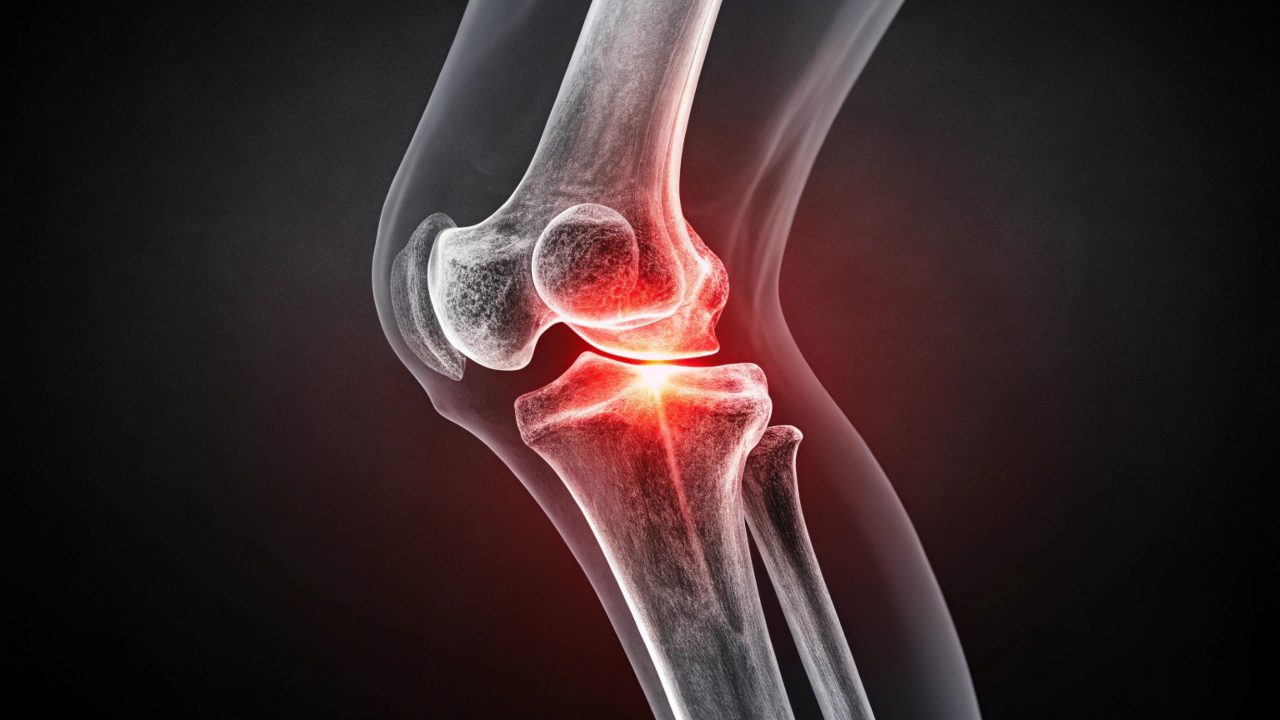

BURTOM Konur Cerrahi Tıp Merkezi Ortopedi ve Travmatoloji Uzmanı Op. Dr. Mehmet Akif Çuhadar, her yaştan insanı etkileyen yaygın sorunlardan biri olan diz ağrılarının ortopedi polikliniklerine yapılan başvurular arasında ilk sırada yer aldığını belirterek, "Diz ağrısına eşlik eden eklemde şişlik, kızarıklık, sertlik, ateş gibi belirtiler varsa ve diz ağrısı günlük aktiviteleri engelliyorsa rahatsızlık ilerlemeden doktora başvurulması gerekir" dedi.

Op. Dr. Mehmet Akif Çuhadar, menisküs yırtıkları, ön çapraz bağ kopmaları, diz kapağı kıkırdak sorunları ve diz kireçlenmesi gibi sık görülen rahatsızlıklar hakkında değerlendirmelerde bulundu.

Op. Dr. Çuhadar, diz ekleminin yapısı gereği büyük bir yük taşıdığını ve iç-dış menisküsler ile ön-arka çapraz bağların eklem stabilitesinde kritik rol üstlendiğini aktararak, ani burkulma ve dönme hareketleri sırasında en sık menisküs yırtıklarının görüldüğünü ifade etti. Menisküs yırtıklarının; ağrı, takılma hissi, merdiven inip çıkarken zorlanma ve bazı hastalarda eklemde kilitlenme gibi belirtilerle kendini gösterdiğini belirten Op. Dr. Çuhadar, tanıda fizik muayene ve MR görüntülemenin birlikte değerlendirildiğine dikkat çekti.

Günümüzde menisküs tedavisinde genellikle artroskopik (kapalı) cerrahinin tercih edildiğini vurgulayan Op. Dr. Çuhadar, diz içine küçük kesilerden yerleştirilen kamera ve özel cerrahi aletler sayesinde hem tanının doğrulandığını hem de yırtık bölgenin onarıldığını, çoğu vakada yırtık kısmın çıkarıldığını; iyileşme potansiyeli olan seçilmiş olgularda ise menisküs tamirinin mümkün olduğunu kaydetti.

Özellikle sporcularda yaygın görülen ön çapraz bağ kopmalarına da değinen Op. Dr. Çuhadar, dizde şiddetli şişlik, boşalma hissi ve kontrol kaybının tipik belirtiler arasında yer aldığını ifade ederek, kesin tanının MR ile doğrulandığını, aktif yaşam sürdüren ve dizde instabilite yaşayan hastalarda ön çapraz bağ rekonstrüksiyonunun artroskopik yöntemlerle gerçekleştirildiğini belirtti. Bu ameliyatlarda hastanın kendi tendonlarının kullanıldığı bilgisini paylaştı.

Diz kapağı kıkırdak aşınmalarının da önemli bir sorun olduğunu dile getiren Op. Dr. Çuhadar, merdiven çıkma, uzun süre oturma ve çömelme gibi hareketlerde artan ön diz ağrısının bu tabloyu işaret ettiğini söyleyerek, kilonun kıkırdak üzerindeki baskıyı artırdığını hatırlatarak, uygun egzersiz programları, özel dizlikler ve kıkırdak yapısını destekleyici tedavilerin başarılı sonuçlar sunduğunu aktardı.

İleri yaşta daha sık görülen diz kireçlenmesinin eklem deformitesine, hareket kısıtlılığına ve dinlenme ağrılarına neden olabildiğini; tedavi sürecinde egzersiz, kilo kontrolü, ilaç uygulamaları, enjeksiyon tedavileri ve fizik tedavinin önemli yer tuttuğunu ifade eden Op. Dr. Çuhadar, ileri düzey kireçlenmelerde ise total diz protezi ameliyatının gündeme geldiğini, bu cerrahiyle hasarlı eklem yüzeylerinin çıkarılıp yerine özel protezlerin yerleştirildiğini belirtti.